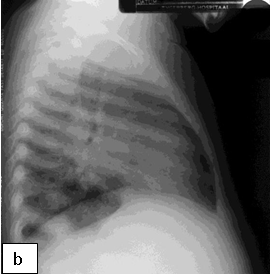

Chest x-ray is not usually diagnostic but may show bilateral diffuse parenchymal infiltrates with a “ground-glass” or reticulogranular appearance, but can be normal or have only mild parenchymal infiltrates. The earliest infiltrates are perihilar, progressing peripherally before reaching the apical portions of the lung.

Chest X-ray (CXR): TB enlarged perihilar lymph nodes are better visualised on a lateral CXR than a PA view, therefore, it is important to obtain both PA and lateral films when evaluating a child with suspected TB.